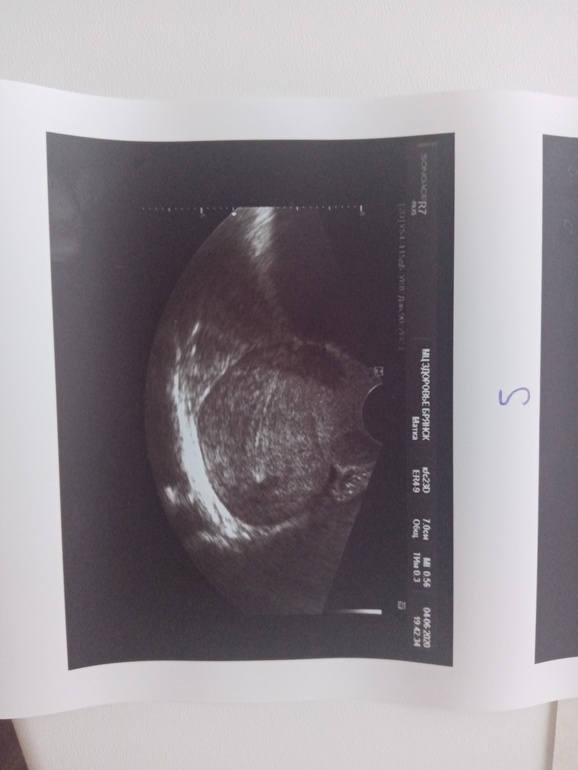

Сегодня попала наконец на узи.

УЗИ прилагаю, жду помощи